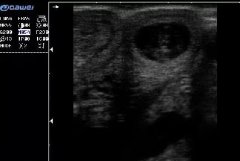

獸用B超在動物中的應用